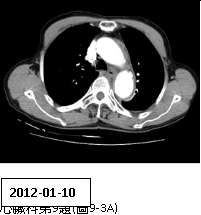

9. 男性病人,72歲,因尖銳性上背部疼痛突然發作,同時伴有急促呼吸及眩暈,乃往急診求治。時,血壓149/91 mmHg;心跳,70/min; RR, 20/min;其他理學檢查並無任何異常。病人每天抽煙一包,已有五十多年。Chest X-ray、ECG及CT,如圖9-1、圖9-2、圖9-3A及圖9-3B後,及其初步處置,後轉送加護病房途中,又突發後背疼,同時雙腳麻及疼痛,並呈現雙腳發紺,乃急照另次CT如圖9-4所示。請問下列何者決策不恰當? (A) 控制心收縮血壓在100-120 mmHg及心跳60-80/min (B) 靜脈注射Labetalol 30 mg/min (C) 口服Propranolol 20 mg tid po (D)口服Aspirin 100 mg qd 及Clopidogrel 75 mg qd (E) 外科會診,緊急手術